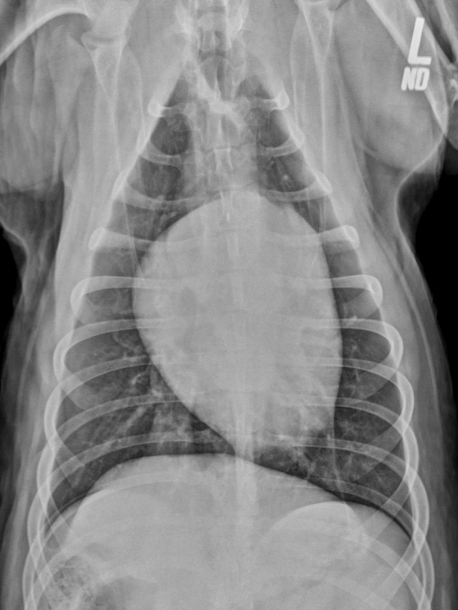

Esophageal dilation